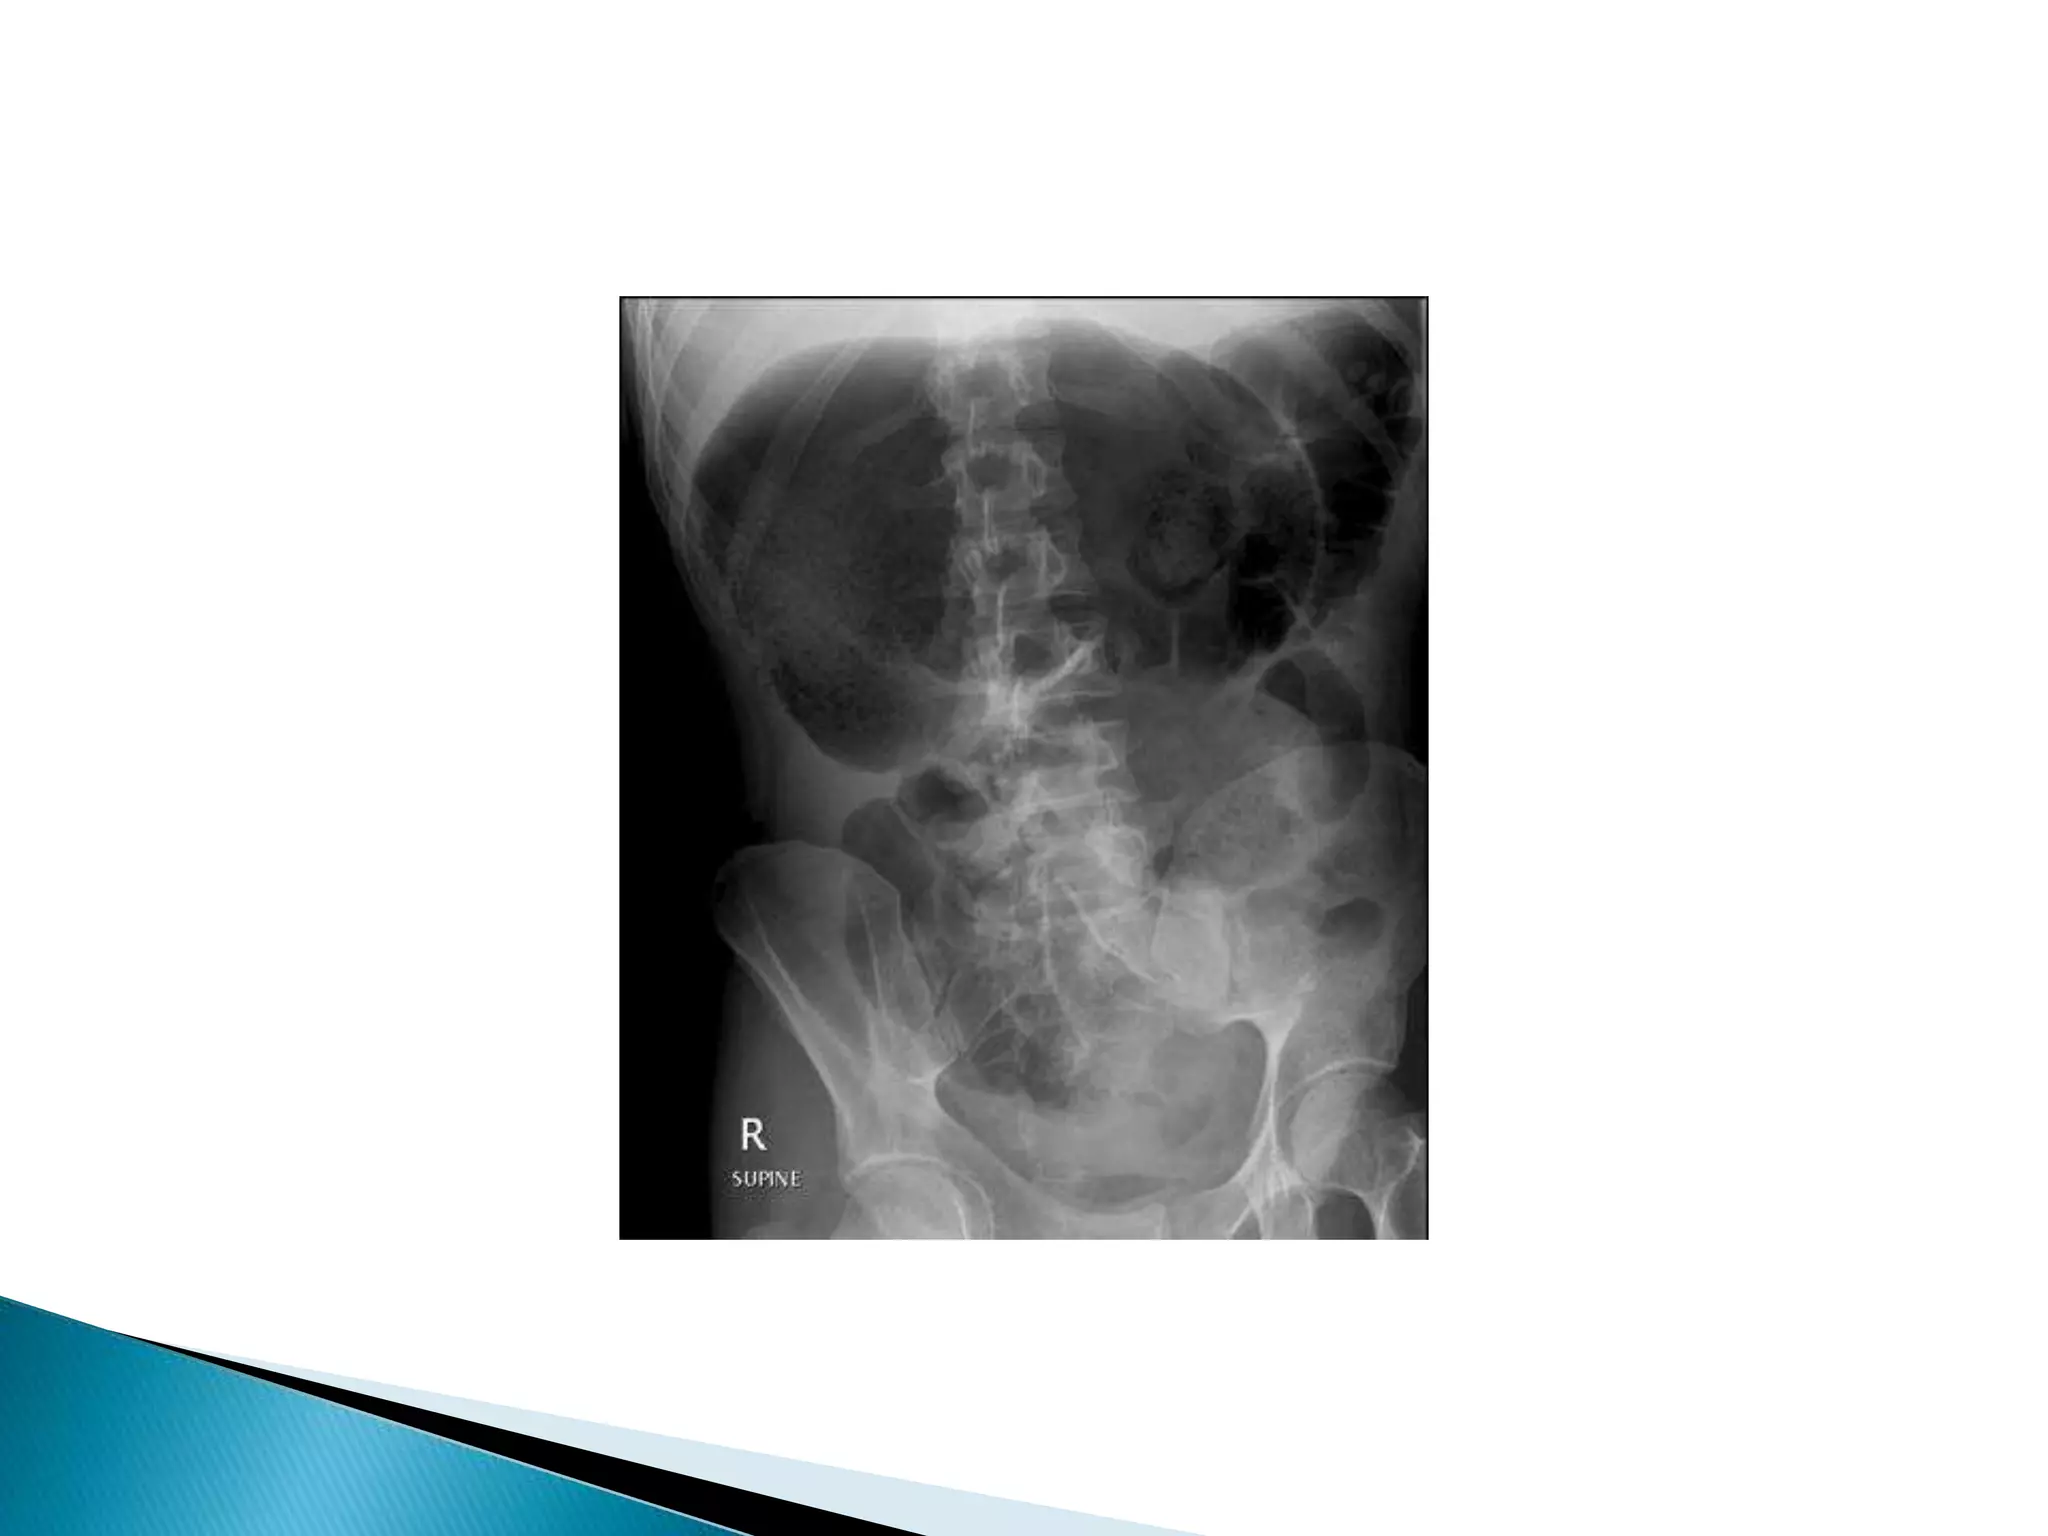

• Bowel loop points to LUQ

• Dilated cecum comes to rest in left upper

quadrant

• Bird’s-beak or bird-of-prey sign à seen on

barium enema as it encounters the volvulated

loop

• CT scan useful in assessing mural wall ischemia

Dilated cecum

Cecum

Contrast

In Descending colon

Barium Enema

Point of Obstruction

Ascending colon